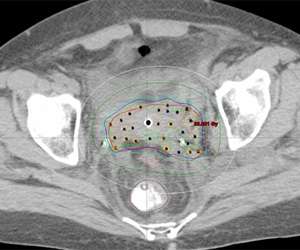

Below is a 3D rendering of the distribution of radiation dose and normal tissues from a gynecologic interstitial implant:

An axial CT slice showing the distribution of small hollow brachytherapy tubes and the distribution of radiation dose for a gynecologic interstitial brachytherapy implant.